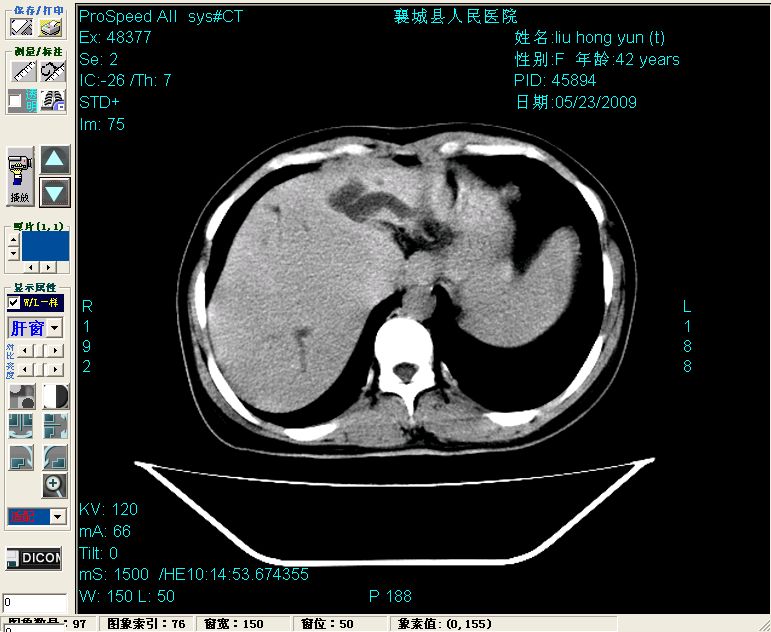

增强:

增强动脉期前述低密度区轻度早其强化,门脉期强化程度显著增高,延期扫描强化程度下降,但仍为相对高密度影

胰头部见结节状高密度影,其前方略可分辨扩强胆部管,平扫到增强始终有,但现在尚难与胃肠造影剂鉴别.

结合病史考虑,1现在引起黄疸体征的原因应该是胆总管胰段结石阻塞,建议局部胃肠造影剂排空后复查.

2左肝及右肝前叶表现考虑胆囊摘除术后所致的肝动门脉瘘形成,慢性纤维组织炎性增生.不完全除外左肝胆管细胞癌